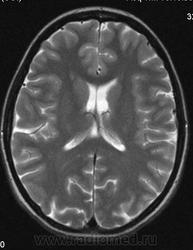

Можно ли  трактовать участок повышенного МР-сигнала по Т2 в правой лобной доле как участок перивентрикулярного глиоза?

Привожу сканы женщины 28 лет без особых жалоб (первые три скана).

Большое спасибо. Да, симметричная линейная паравентрикулярная структура в области передних рогов встречается часто, на что обычно не обращаю внимания. В этом случае смутила ее асимметричность (особенно на Coг. срезах), если думать что это Вирхова-Робина, то возможно это слабо выраженный периваскулярный глиоз.